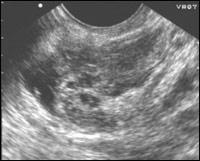

| Рисунок 2

| Эхокартина внематочной беременности Внематочная беременность в интрамурально-истмическом отделе.